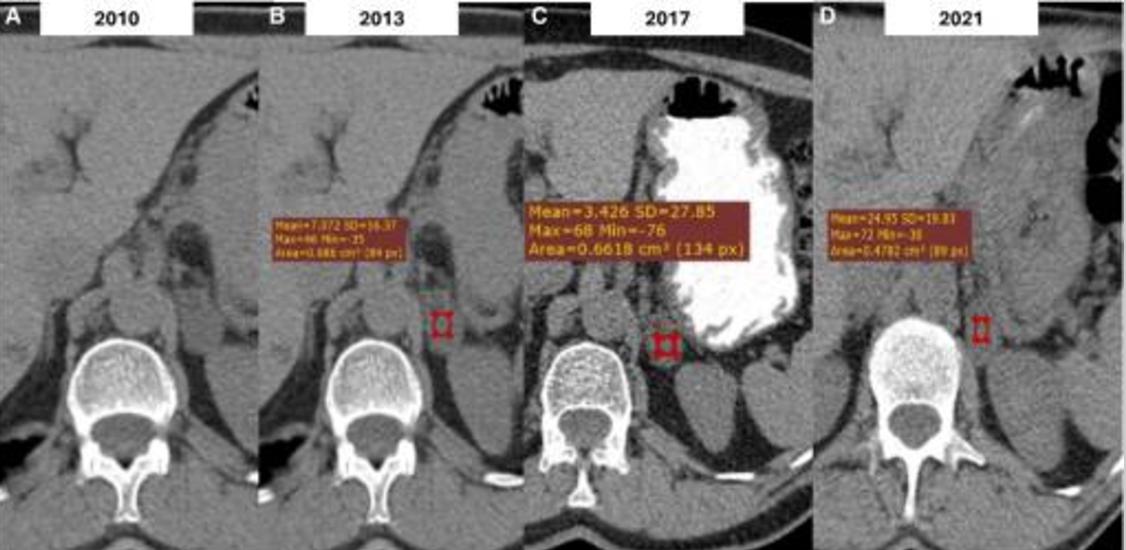

2010年,一名有高血压病史的64岁男性吸烟者因腹部不适进行腹部CT检查后,被偶然诊断出左肾上腺有3厘米的同质病变。病变密度<10HU,因此倾向于ACA。激素检查显示没有激素分泌过多的证据。患者在前3年每年接受腹部CT,然后每2年随访一次。病变的大小和影像学特征一直保持稳定,直到2017年失访。

2021年进行的CT扫描显示,病变稳定,为3cm,但非增强衰减值较高,为24HU(图1)。激素筛查显示没有激素分泌过多。2年后,患者在3个月内体重明显减轻,伴有疲劳和腹痛。腹部CT显示,左侧肾上腺存在12×11.5×8.6 cm的异质性病变,表现为周围结构弥漫性浸润(图2)。

图1 上腹部轴向非增强计算机断层扫描(CT)图像显示,左侧肾上腺结节状病变大小为3cm,低衰减值<10HU,与腺瘤一致(a)。同一患者的随访CT图像显示,病变的大小或密度没有显著变化,平均值±标准差密度值等于7±16.37 HU(最大=46,最小=-35)(B)和3.4±27.85 HU(最大=68,最小=-76)(C)。在肾上腺皮质癌(ACC)诊断前一年进行的随访CT中,病变的大小保持稳定,但显示出较高的平均值±标准差密度值,等于24±19.83 HU(D)